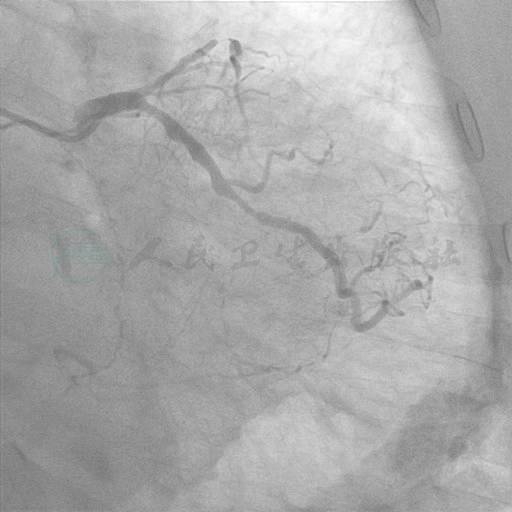

冠状动脉造影结果

选用右侧桡动脉径路,6F血管鞘。造影发现(图1~图3):左主干未见明显狭窄或阻塞性改变,前降支起始部100%闭塞,远端可见来自回旋支侧支循环。回旋支近中段弥漫性病变,狭窄最重90%。右冠状动脉:近段100%闭塞。

图1 右冠造影

图2 左冠造影1

图3 左冠造影2